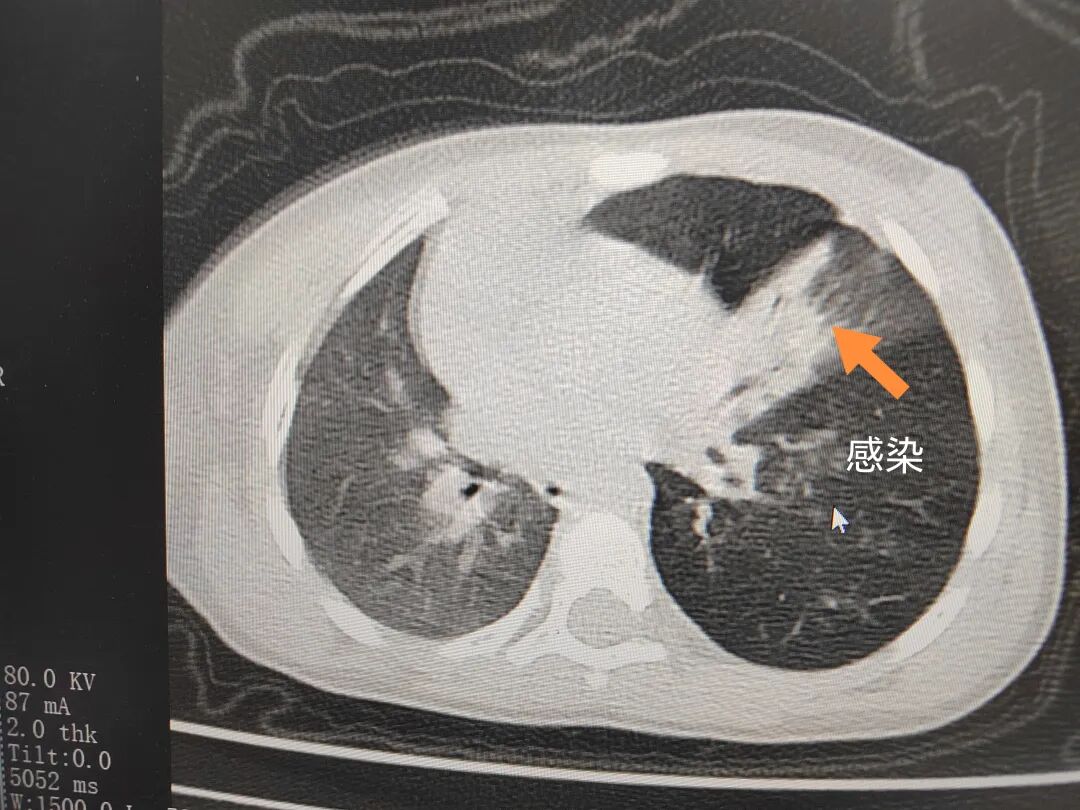

三天后(11月13日),趙寶出現高熱、咳喘加重,家長著急了,再次帶他來到醫(yī)院。CT檢查顯示左肺過度充氣,左肺上下葉支氣管主干見不規(guī)則高密度影,左肺上葉可見大片狀密度增高影,縱隔窗實變,提示為“左側支氣管內異物并繼發(fā)性改變,左肺上葉舌段肺膨脹不全”。

市二院小兒呼吸內科團隊迅速為患兒制定了周密的手術方案,并很快安排了氣管鏡探查。術中,主治醫(yī)師田慧等憑借嫻熟的氣管鏡操作技術成功將異物大塊板栗取出。由于板栗在氣管內存留時間較長,質地軟糯易碎,大大增加了手術難度。檢查還發(fā)現,異物停留部位的氣管黏膜已出現充血紅腫、糜爛,導致患兒住院時間相應延長。此次事件給趙寶的家庭帶來了不小的驚嚇與擔憂,也再次為廣大家長敲響了警鐘。

市二院小兒呼吸內科副主任楊亞娟介紹,異物誤入氣道可能導致氣道阻塞,嚴重時可引發(fā)窒息,甚至危及生命。若異物進入支氣管,造成不完全堵塞,可引起阻塞性肺氣腫;如完全堵塞支氣管,則可能導致肺組織萎縮,形成肺不張。此外,若異物存留時間較長,或為植物性異物,容易合并細菌感染,產生膿性分泌物,進而發(fā)展為肺炎。她強調,盡早診斷并取出異物,是減少并發(fā)癥、降低病死率的關鍵。